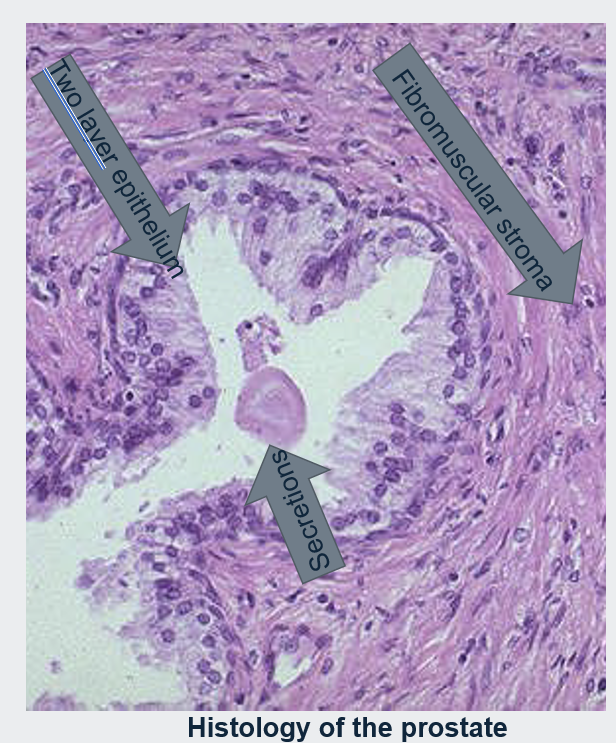

Prostate Histology

Histologically the prostate is composed of glands lined by two layers of cells.

A basal layer of low cuboidal epithelium covered by a layer of columnar secretory cells.

In many areas there are small papillary infoldings of the epithelium.

These glands are separated by abundant fibromuscular stroma.